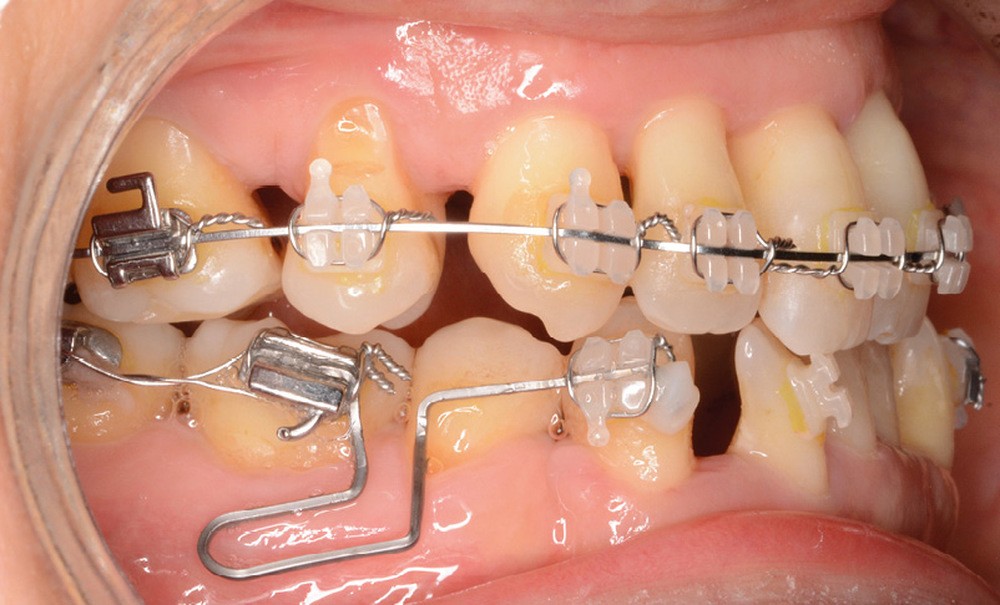

Un traitement en technique vestibulaire par appareillage multi-attaches .022 x .028 inch (prescription selon Roth) est entrepris, avec avulsion de prémolaires (15, 25, 34, 44).

La patiente ne supportant aucune cale occlusale, le collage de l’arcade mandibulaire est séquentiel afin de ne placer aucune attache en interférence occlusale. Le recul canin mandibulaire se fait grâce à des arcs sectionnels à boucle en Titane-Molybdène (TMA) .017 x .025 (fig. 10).

L’alignement et le nivellement maxillaires sont conduits en arc droit, et la mésialisation molaire réalisée en glissement, soutenue par des élastiques inter-arcades de classe III.

Le nivellement mandibulaire par ingresssion des incisives est mené via des arcs acier à la déformation avant de pouvoir recoller les brackets incisifs dans une position permettant de terminer le traitement en arc droit (fig. 11).